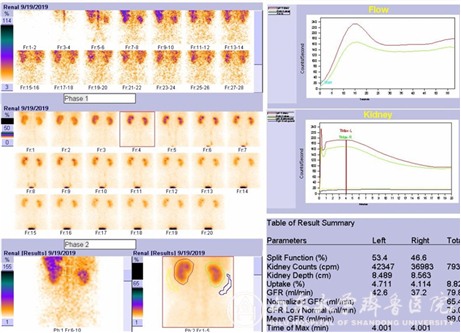

在早期诊断冠心病心肌缺血、评价心肌储备功能、估测冠心病患者受累血管供应区域心肌缺血范围与程度、评价心肌梗死、冠脉搭桥术术前病例选择及术后疗效评估及冠心病治疗后疗效观察等方面均具有重要意义。此外,这是唯一能评价单侧肾功能的检查方法,新机器进一步根据病人的身高体重进行修正,可以获得更加精确的“标准化”肾小球滤过率值(Normalized GFR)。